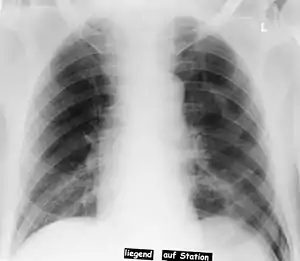

| Pneumothorax left sided | |

| Differential diagnosis | pneumothorax |

In radiology, the deep sulcus sign on a supine chest radiograph is an indirect indicator of a pneumothorax.[1][2] In a supine film, it appears as a deep, lucent, ipsilateral costophrenic angle[3] within the nondependent portions of the pleural space as opposed to the apex (of the lung) when the patient is upright. The costophrenic angle is abnormally deepened when the pleural air collects laterally, producing the deep sulcus sign.[4]

Patients with chronic obstructive pulmonary disease (COPD) may exhibit deepened lateral costophrenic angles due to hyperaeration of the lungs and cause a false deep sulcus sign.